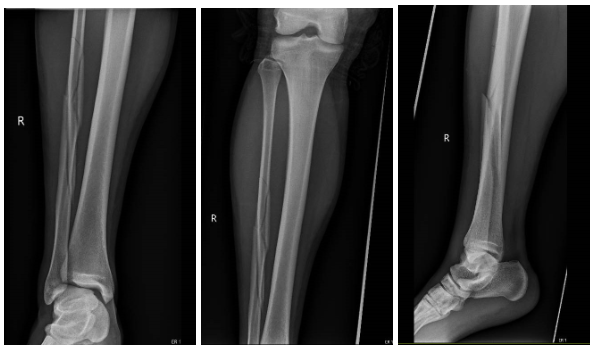

Here are the Tib-Fib x-rays for the patient:

Image E, F, G: Right Tibia-Fibula x-ray (Lateral with ankle, lateral with knee, AP)